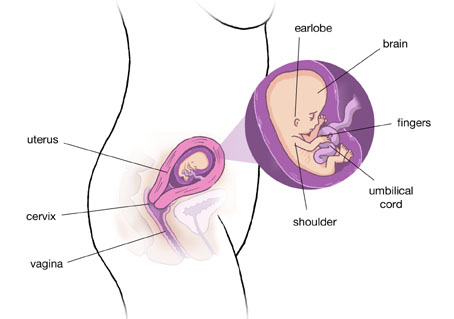

Ваш малюк зараз розміром з полуницю. При вагітності 10 тижнів розмір плода становить близько 3-4,5 см, а його вага - близько 5 м Він ще непропорційний, у нього велика голова, вже сформовані ручки і ніжки. Шкіра ще зовсім прозора, і через неї добре проглядаються кровоносні судини. Ваш малюк вже активний, добре рухає ручками та ніжками.

10-11 тиждень вагітності - етап завершення органогенезу. Далі відбувається вдосконалення всіх систем організму малюка. На цьому етапі вже сформувалася діафрагма, і грудна порожнина крихти відокремилася від черевної. Уже сформовано четирехкамерное серце, яке активно б'ється.

Щодня розвиваються нові і нові нейрони, вдосконалюється нервова система. Головний мозок малюка ще не має звивин, але кора вже диференційована. Зовсім скоро нервова система дозволятиме малюкові управляти своїм тілом, і рухи стануть цілеспрямованими.

Пальчики малюка вже практично розділені між собою. Сформовані великі суглоби, які поки мають хрящову структуру. Малюк вже вміє рухати ручками, ніжками, може відштовхуватися від стінок матки, але поки згинати пальчики не може.